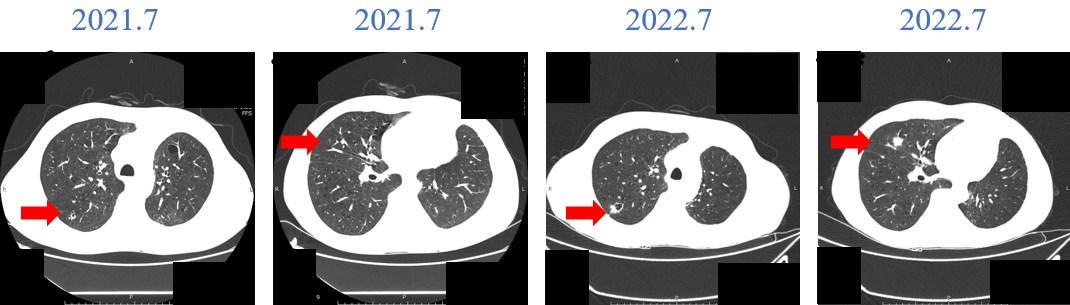

疗效评价:复查CT(2022-07-11),肿块从9.4cm缩小至5.4cm,评估为部分缓解(PR),肺内转移灶及纵隔淋巴结均较前缩小。

复查CT(2022-11-29):肿块5.2cm(缩小),仍维持PR状态,肺内结节缩小至0.5cm,淋巴结部分缓解并出现坏死性改变。